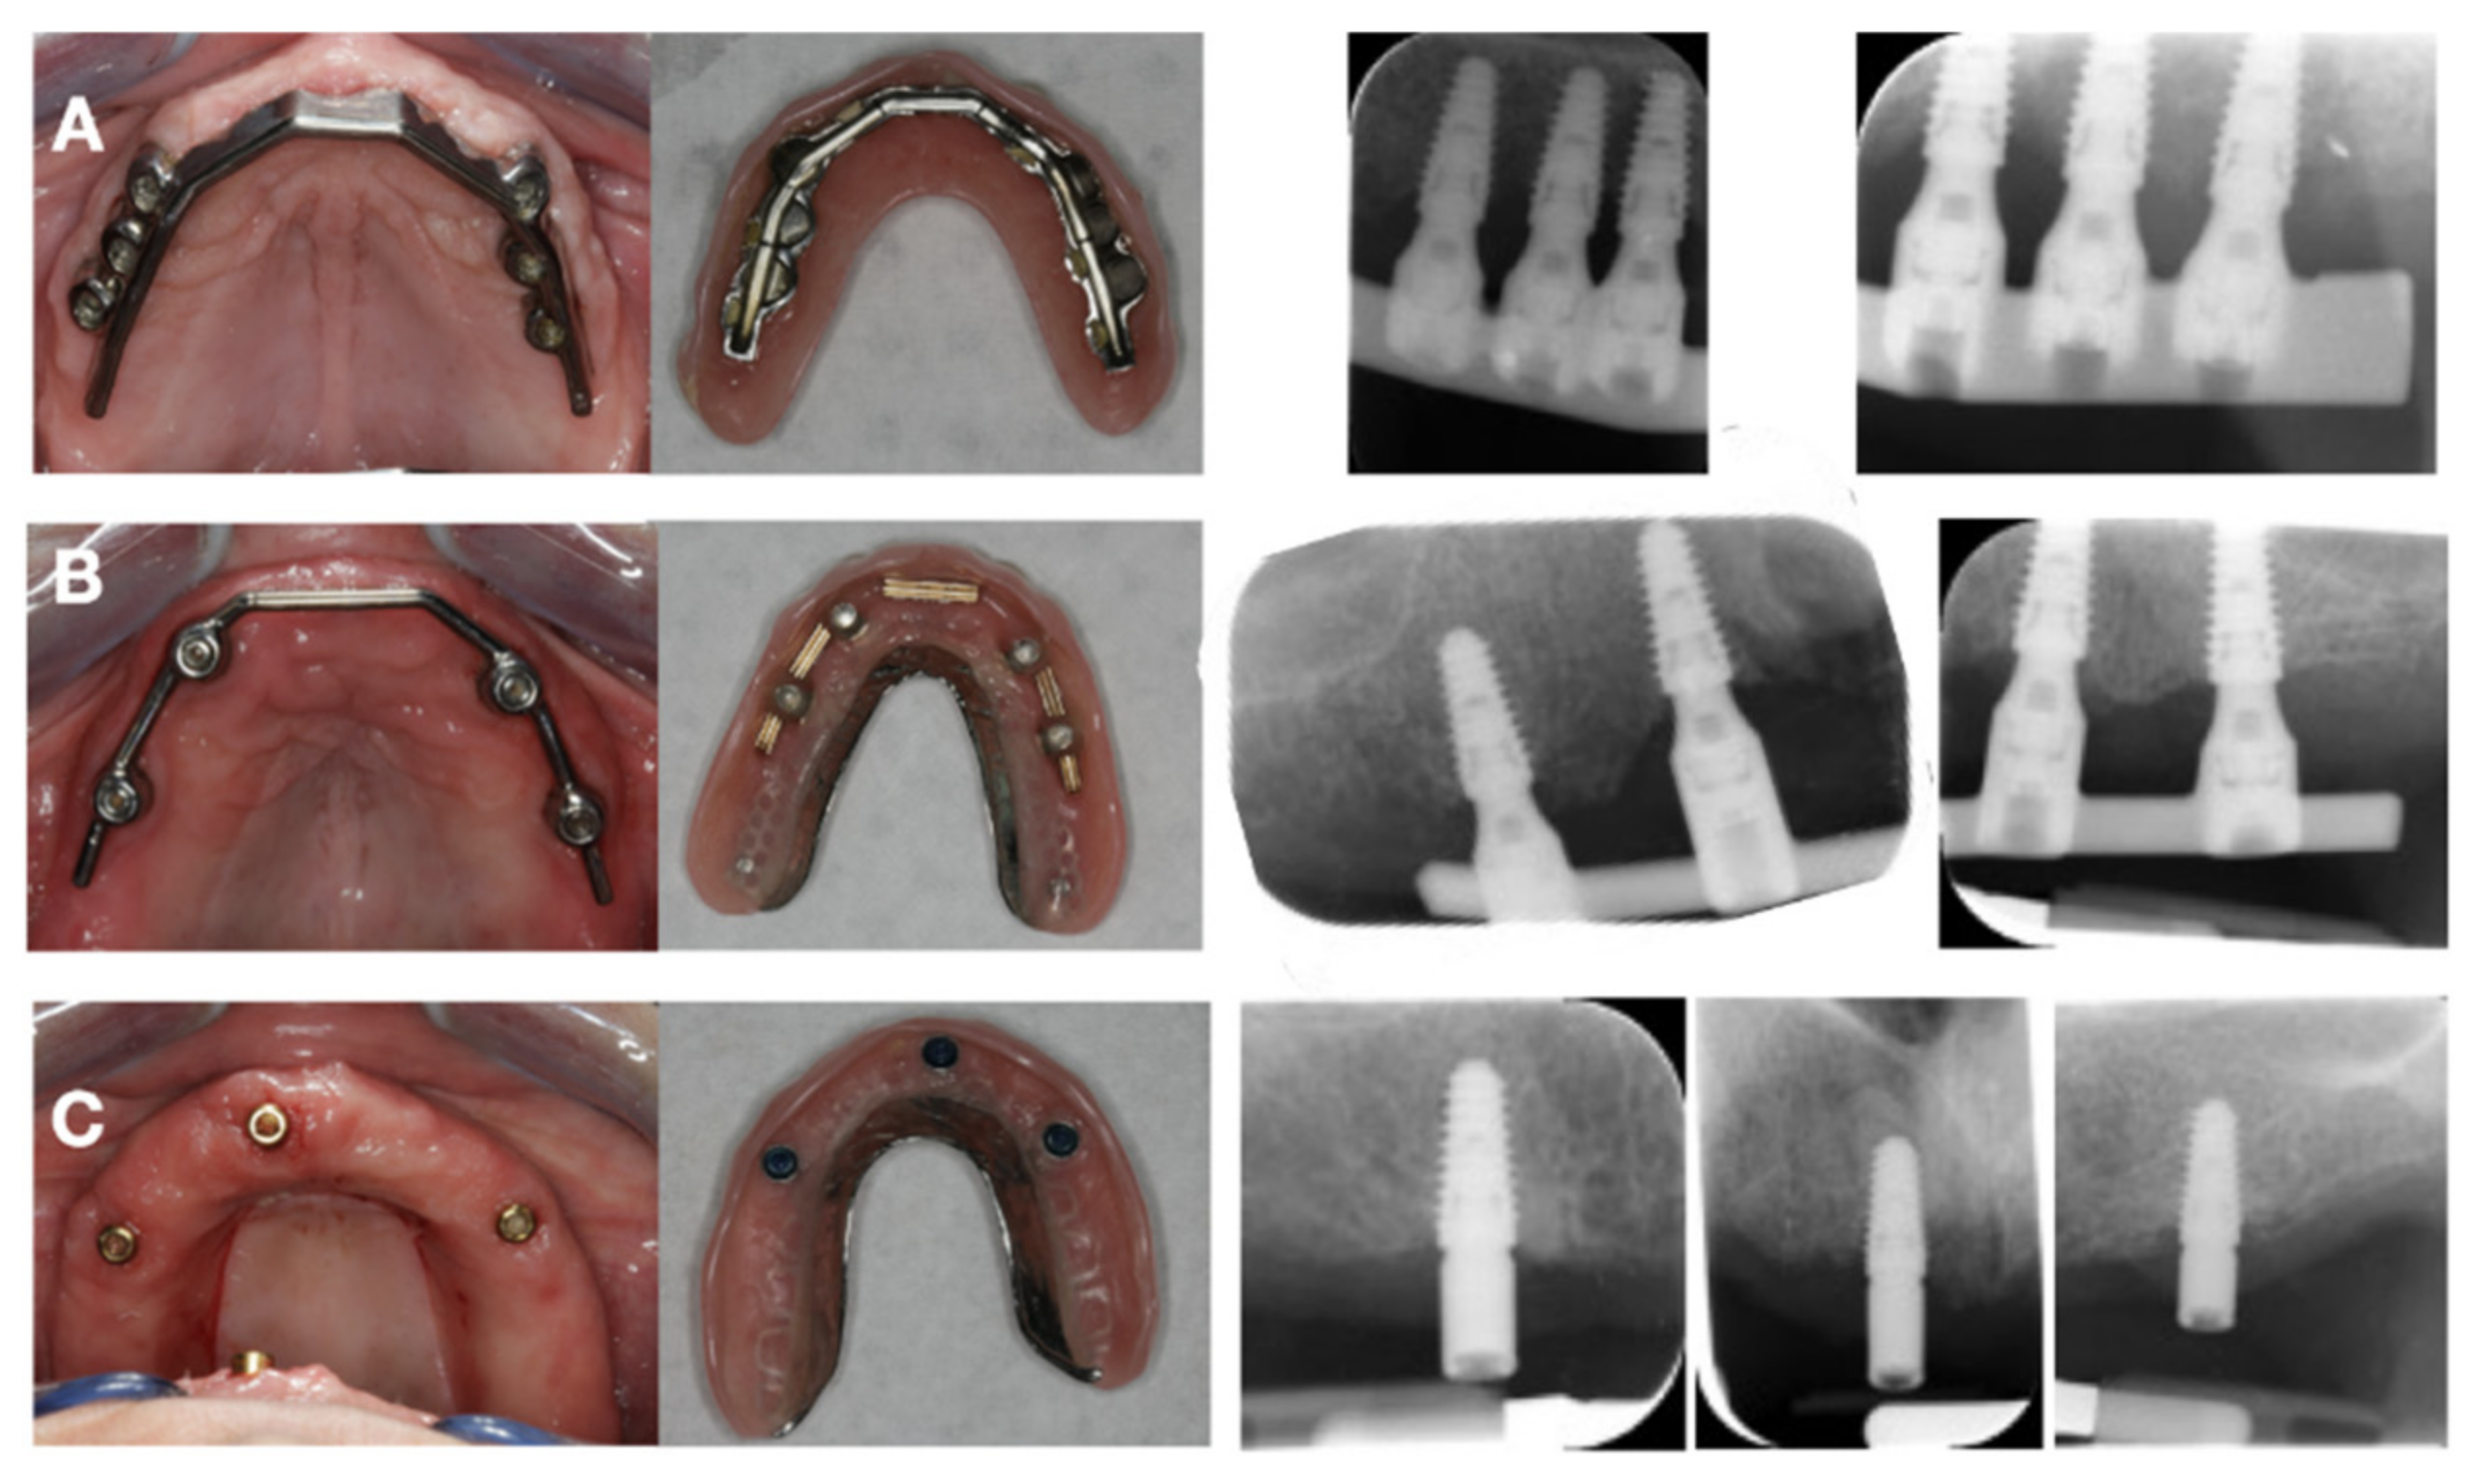

2. Materials and Methods

2.1. Patient Selection and Treatment Allocation

2.2. Surgical and Prosthetic Procedure